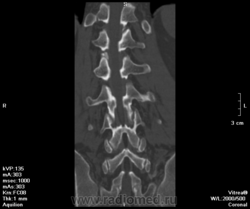

Остеопороз. Спондилодисцит (репоративная стадия?). Спондилоартроз. Деф.спондилоз. Грыжа L IV-V, распространяющаяся на правое межпозвонковое отверстие . Протрузия LV-SI.

1973 г.р. Автослесарь. Жалобы на боли в пояснице и правой ноге. С-реактивного белка в направлении нет, анамнез не описан.

Остеоходроз. Грыжи Шморля. Данных за спондилит и остеопороз не вижу.

У первого пациента грыжа Шморля. Данных за туберкулез я не вижу: контуры замыкательных пластинок четкие, структура окружающей ткани позвонков не нарушена, натечников нет.

Бывает, конечно, что по этому поводу голову ломаешь - деструкция ли это, или только шморлевские узелки. Но здесь все четко.

а что с верхней пластинкой L5? И L4 тоже. откуда такая узурация, особенно в передней части позковнка. неужто шморля?

Да, узелки Шморля в верхней пластинке. Лордоз выпрямлен, но что это доказывает?

Расскажите про Шморля. Чтойто они такие. По представленным второй ряд средний скан L3-L4 задний край -вот я так себе их представляю на КТ. В L4, L5, S1 практически вся поверхность съедена, это они подряд так выстраивются? Ведь если одна, то она углублятся будет, а не по горизонтали распространяться. Может уже что другое там? Перенесенное что-нибудь?

Ну да, подряд выстраиваются))) Как солдаты.

О причинах этого можно рассуждать долго: может быть, все дело в остеопорозе, может, в нестабильности. Бог знает. Главными дифференциально-диагностическими признаками здесь служат четкость кортикального слоя и отсутствие мягкотканных изменений.